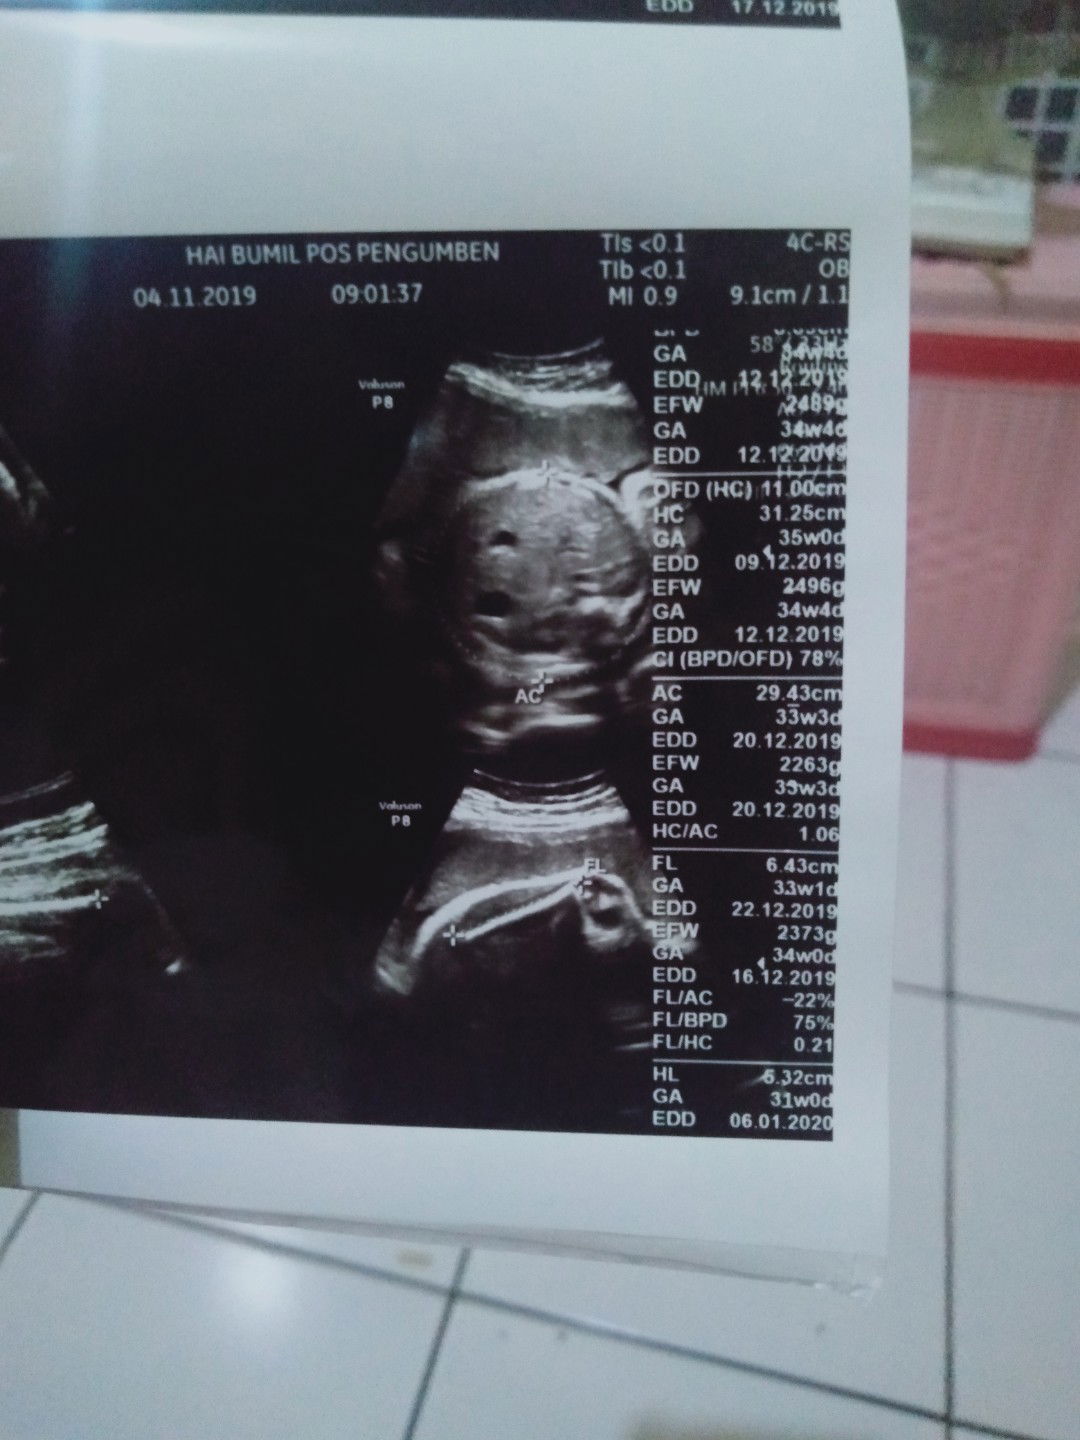

Bun ada yg kaya saya ga lingkar kepala sma perut beda lebih besar lingkar kepala bun saya kepikiran bgttt usia kehamilan 33w,lingkar kpla 35w klo lingkar perut 33w

Bunn kmren saya usgg trss diungkur lingkar kepalanya trs lingkar perutnyaa tapi kata dokternya lingkar kepalanya beda dngn lingkar perut klo kata dokter aga cenderung besar kepalanyaa apaa ada yang kaya saya bun sedih bgt pas dngrrnyaa bun???